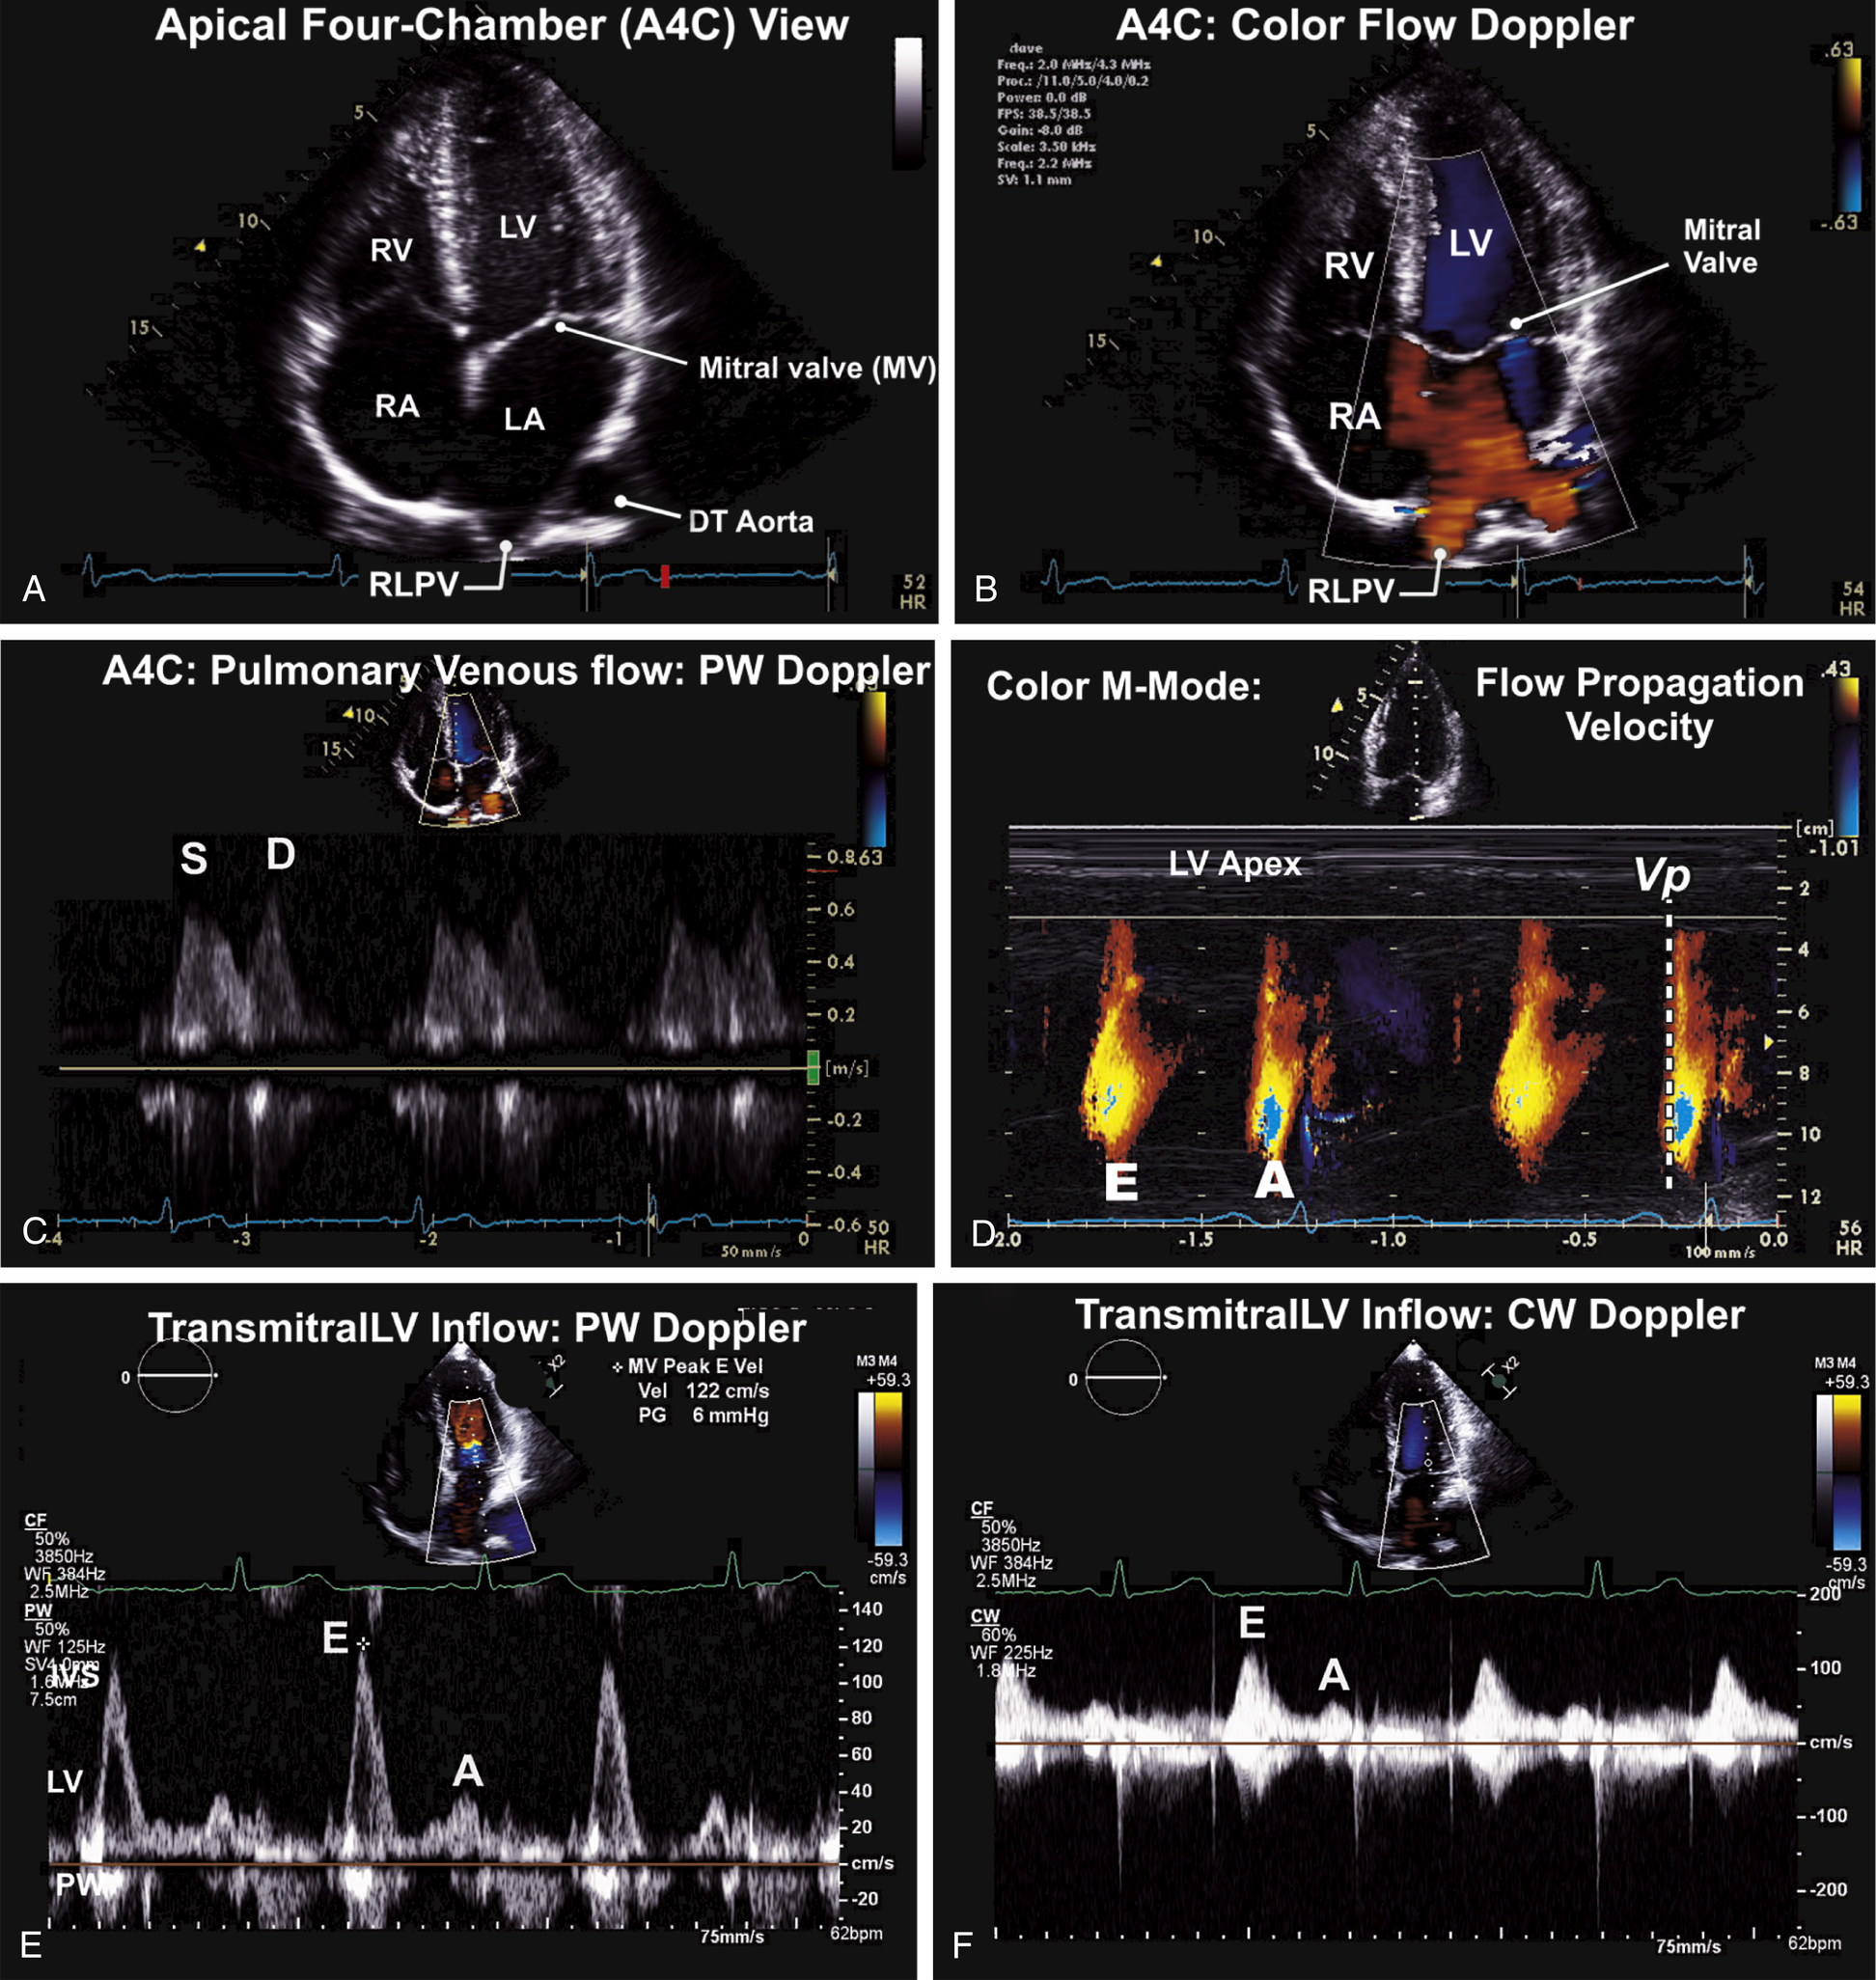

Apical Views (see Figs. 9.5–9.8)

| Transducer Position (Window) | 2d ± M-Mode ± 3d | CFD | Spectral Doppler Pw, Cw | Tissue Doppler Imaging (Tdi) |

| Apical four-chamber (A4C) | 2D image; depth 15–16 cm. 2D Measurement of LA volume- measure LA volume at the end of systole and the shorter length of the LA 3D full-volume (optional) Evaluate RV function on 2D focus RV image. TAPSE (tricuspid annular plane systolic excursion) | CFD to MV for MR, MS CFD the Pulmonary veins, PW of right upper or lower pulmonary vein Color M-Mode flow propagation velocity CFD to TV and CW for TR max velocity. | PW Doppler at the tips of the mitral leaflets for MV inflow CW Doppler of the MV | TDI (PW) of MV annulus (lateral and septal) Color TDI to LV walls TDI of TV annulus |